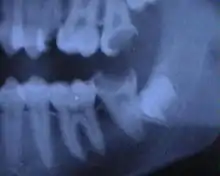

Cette infection peut être chronique : granulome péri-apical chronique ou kyste (ou desmodontite apicale chronique). L'infection évolue alors souvent à bas bruit pendant plusieurs mois voire plusieurs années, et n'est parfois détectée que par un contrôle radiographique de routine. Cette infection peut aussi être aiguë : abcès péri-apical aigu (ou desmodontite apicale aiguë). Voir : Endodontie.

Les dentistes utilisent désormais un détecteur de densité pour mesurer l'ampleur d'une déminéralisation de la dent, cela permet d'éviter une irradiation pour effectuer une radiographie.

Le dépistage de petites lésions dispose de trois techniques d’examen complémentaires à l'œil du dentiste : radio numérique en 2D, aides optiques de grossissement (loupes ou microscope opératoire), caméra vidéo numérique de fluorescence ou de transillumination [33].